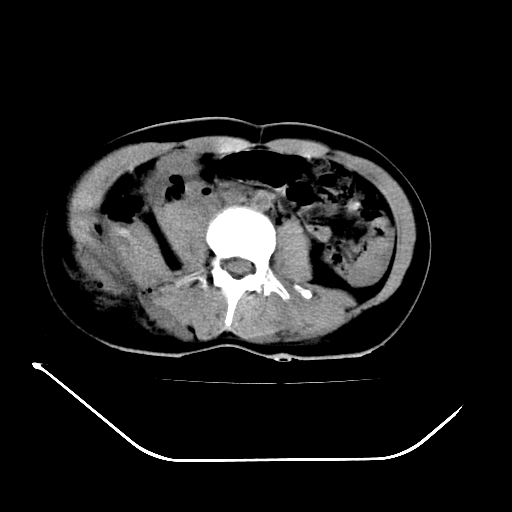

以下是引用liuyue在2008-7-19 13:02:00的发言:[br]1.肝右叶后下段及右肾挫裂伤伴腹腔积血。[br]2.右侧多发性肋骨骨折、横突骨折、右髂骨骨折伴周围软组织挫伤。[br]3.右侧腰大肌肿胀,并可见低密度影,如为气体,则肠道挫裂伤待除外。

以下是引用zhengfaming在2008-7-19 14:42:00的发言:[br]1.肝右叶后下段及右肾挫裂伤伴腹腔积血。脾脏挫裂伤待排[br]2.右侧多发性肋骨骨折、横突骨折、右髂骨骨折伴周围软组织挫伤。[br]3.右侧腰大肌肿胀,并可见低密度影,如为气体,则肠道挫裂伤待除外

以下是引用道哥在2008-7-19 16:52:00的发言:[br]肝右叶后下段及右肾挫裂伤、脾破裂伴腹腔积血。[br]2.双侧多发性肋骨骨折、横突骨折、右髂骨骨折伴周围软组织挫伤。[br]3.右侧腰大肌肿胀,并可见低密度影,如为气体,则肠道挫裂伤待除外。